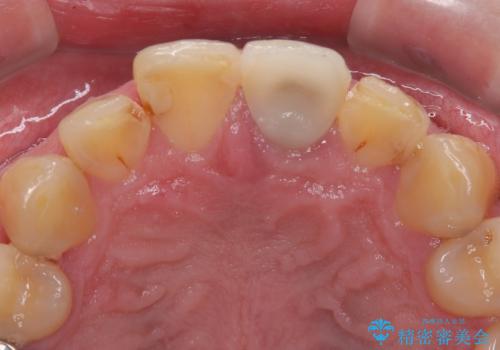

- 前歯の見た目を良くしたいとのことで来院された患者様です。今までに保険のプラスチック(コンポジットレジン)で虫歯の治療をしており経年的な劣化により着色が目立つようになっていました。また歯と歯の隣り合っているところに段差もあり虫歯になっていたり、詰め物も外れていたため前歯4本のオールセラミッククラウンによる治療を行うこととなりました。

拡大鏡視野下で保険のプラスチック(コンポジットレジン)、虫歯、左上1の被せものを除去し、オールセラミッククラウンに適した形にしました。